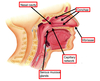

Label the diagram

Label the diagram

What goes down each of the pipe in the pharynx?

Nasopharynx = air

Oropharynx = food

Laryngopharynx = air and food

During swallowing, what happens to the pharynx to prevent choking?

The soft palate (tissue separating nasal cavity and mouth) closes the nasopharynx and the epiglottis closes and becomes a glottis preventing food form going down the trachea

What is the epiglottis called when it is closed?

Glottis